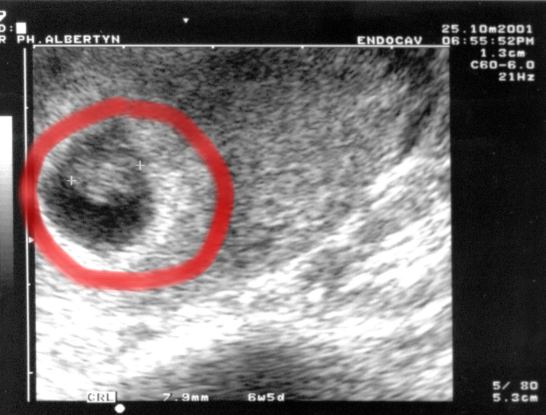

6w 6D: The first echo is undoubtedly the better one, but hey... I got two, I show two.